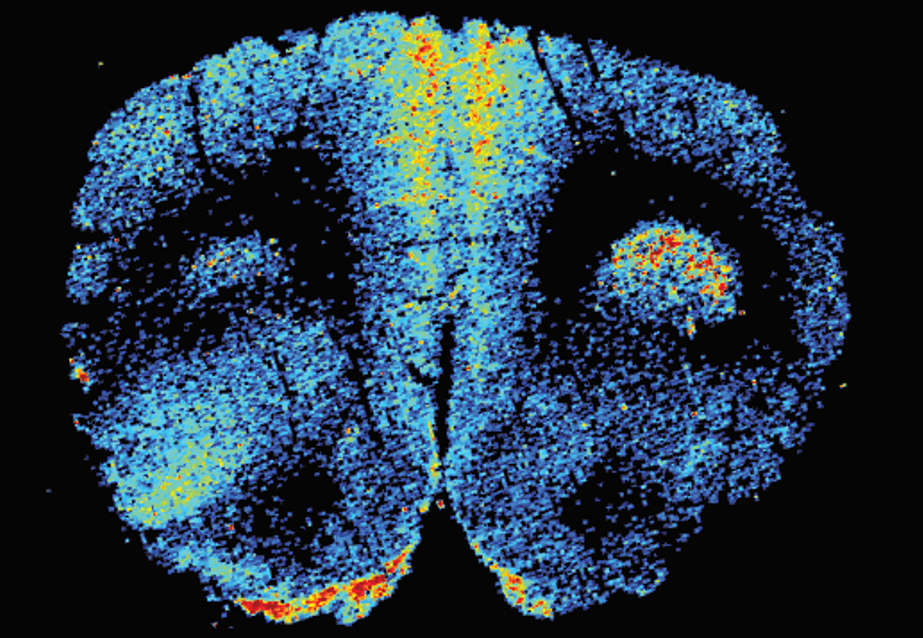

LA-ICP-MS成像技术作为神经科学研究的一个强大的新工具已得到广泛认可并应用到科研领域,这项技术能够对人类和实验动物的大脑进行精确的解剖定位和超痕量元素的定量分析。LA-ICP-MS能够实现准确的元素定性和定量、具有超高的灵敏度(ppb-ppt)和超宽的动态范围,以及高空间分辨率(微米),无需标识或标记。

此外还可以将一个大脑切片同时生成多个元素成像图,通过无处不在的元素,例如磷可被用来定位不同的大脑组织区域,用以区分灰质(神经元、胶质和血管)和白质(神经纤维束);磷元素的成像图极大地促进了其它目标元素(Cu、Zn、Fe、Gd等)的准确定位和含量分布。大脑标本LA-ICP-MS成像技术是一个新颖而强大的工具,可以探索基本大脑机制,加速开发新的诊断方法、治疗方法、药物输送系统,用于治疗神经退行性疾病、脑外伤、脑癌、脱髓鞘疾病、癫痫和其他中枢神经系统疾病。

大鼠和人脑中元素和浓度的分布提供了关于大脑结构和功能的重要信息:

★ 碳成像可以针对肉眼无法检测到的组织成像质量提供重要的信息,诸如组织在加工,切片,和转移过程中的皱纹、褶皱、撕裂等痕迹;

★ 磷在整体大脑中的含量较高,在灰质中的相对富集程度是最高的,其中小神经元的细胞密度最大(如海马的齿状回、小脑的颗粒细胞层),因此磷成像是一个用于区分灰质和白质理想的元素;

★ 铁同位素可用于常规基础脑成像,通过铁成像显示了来自大鼠和人类四个脑区:大鼠前扣带回皮层,大鼠海马,大鼠小脑和人类大脑皮层;